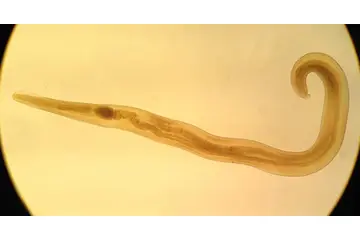

Hamilelikte (gebelikte) Kıl Kurdu Belirtileri ve TedavisiHamilelik, birçok kadının vücudunda çeşitli değişikliklerin meydana geldiği bir dönemdir. Bu süreçte, bazı sağlık sorunları da ortaya çıkabilir. Kıl kurdu, özellikle çocuklarda yaygın olarak görülen bir parazit enfeksiyonudur; ancak hamile kadınlar da dahil olmak üzere her yaş grubunda görülebilir. Bu makalede, hamilelikte kıl kurdu belirtileri ve tedavi yöntemleri ele alınacaktır. Kıl Kurdu Nedir? Kıl kurdu (Enterobius vermicularis), insan bağırsaklarında yaşayan ve genellikle rektum çevresinde bulunan bir parazittir. Enfeksiyon, genellikle hijyen eksikliği veya enfekte birinin temas etmesi ile yayılır. Kıl kurdu, özellikle gece saatlerinde kaşıntıya neden olur ve bu durum, uyku kalitesini olumsuz yönde etkileyebilir. Hamilelikte Kıl Kurdu Belirtileri Hamilelikte kıl kurdu enfeksiyonunun belirtileri, diğer bireylerde görülenlerle benzerlik göstermektedir. Aşağıda, hamilelikte kıl kurdu belirtilerine dair önemli noktalar bulunmaktadır: